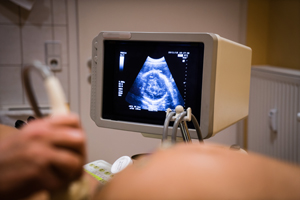

懷孕對于一個女人來說是一件人生大事,可是因為各種各樣的生活原因以及遺傳原因,有可能出現(xiàn)胎兒畸形的情況。面對胎兒畸形的情況,許多孕婦都會驚慌失措,然而只有及時采取合理的補救方法才能夠使損失降到最低。那么當遇到胎兒畸形的時候,我們應(yīng)該怎么辦呢?

胎兒畸形的處理應(yīng)該根據(jù)程度來進行判斷。如果是輕度的畸形,不危及孩子的生命或僅需要小手術(shù),這時孕媽們建議多聽取專家意見,選擇合適的手術(shù)方案。當腹中的胎兒患有嚴重的畸形,如心臟的缺陷,可能危及孩子的生命或留下永久性的殘疾,這時孕媽們應(yīng)該考慮清楚,選擇是否繼續(xù)妊娠。